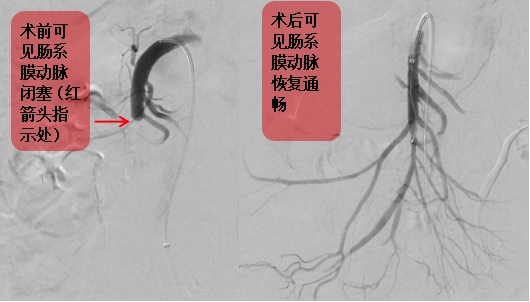

图2  我院介入取栓治疗患者图像1例

本次会议总结了我院近1年来接诊的肠卒中患者,经过不断的改进流程,已形成完善的肠卒中绿色通道,可以实现从确诊开始2小时内急诊手术,手术时可以同时进行胃肠外科微创腹腔镜探查、坏死肠管切除和血管外科最尖端设备的介入取栓治疗,大大减少了患者反复转运的不便,避免了相关科室之间衔接不畅的种种问题,使得患者围术期的死亡率大幅下降至20%左右,达到了国际领先水平。